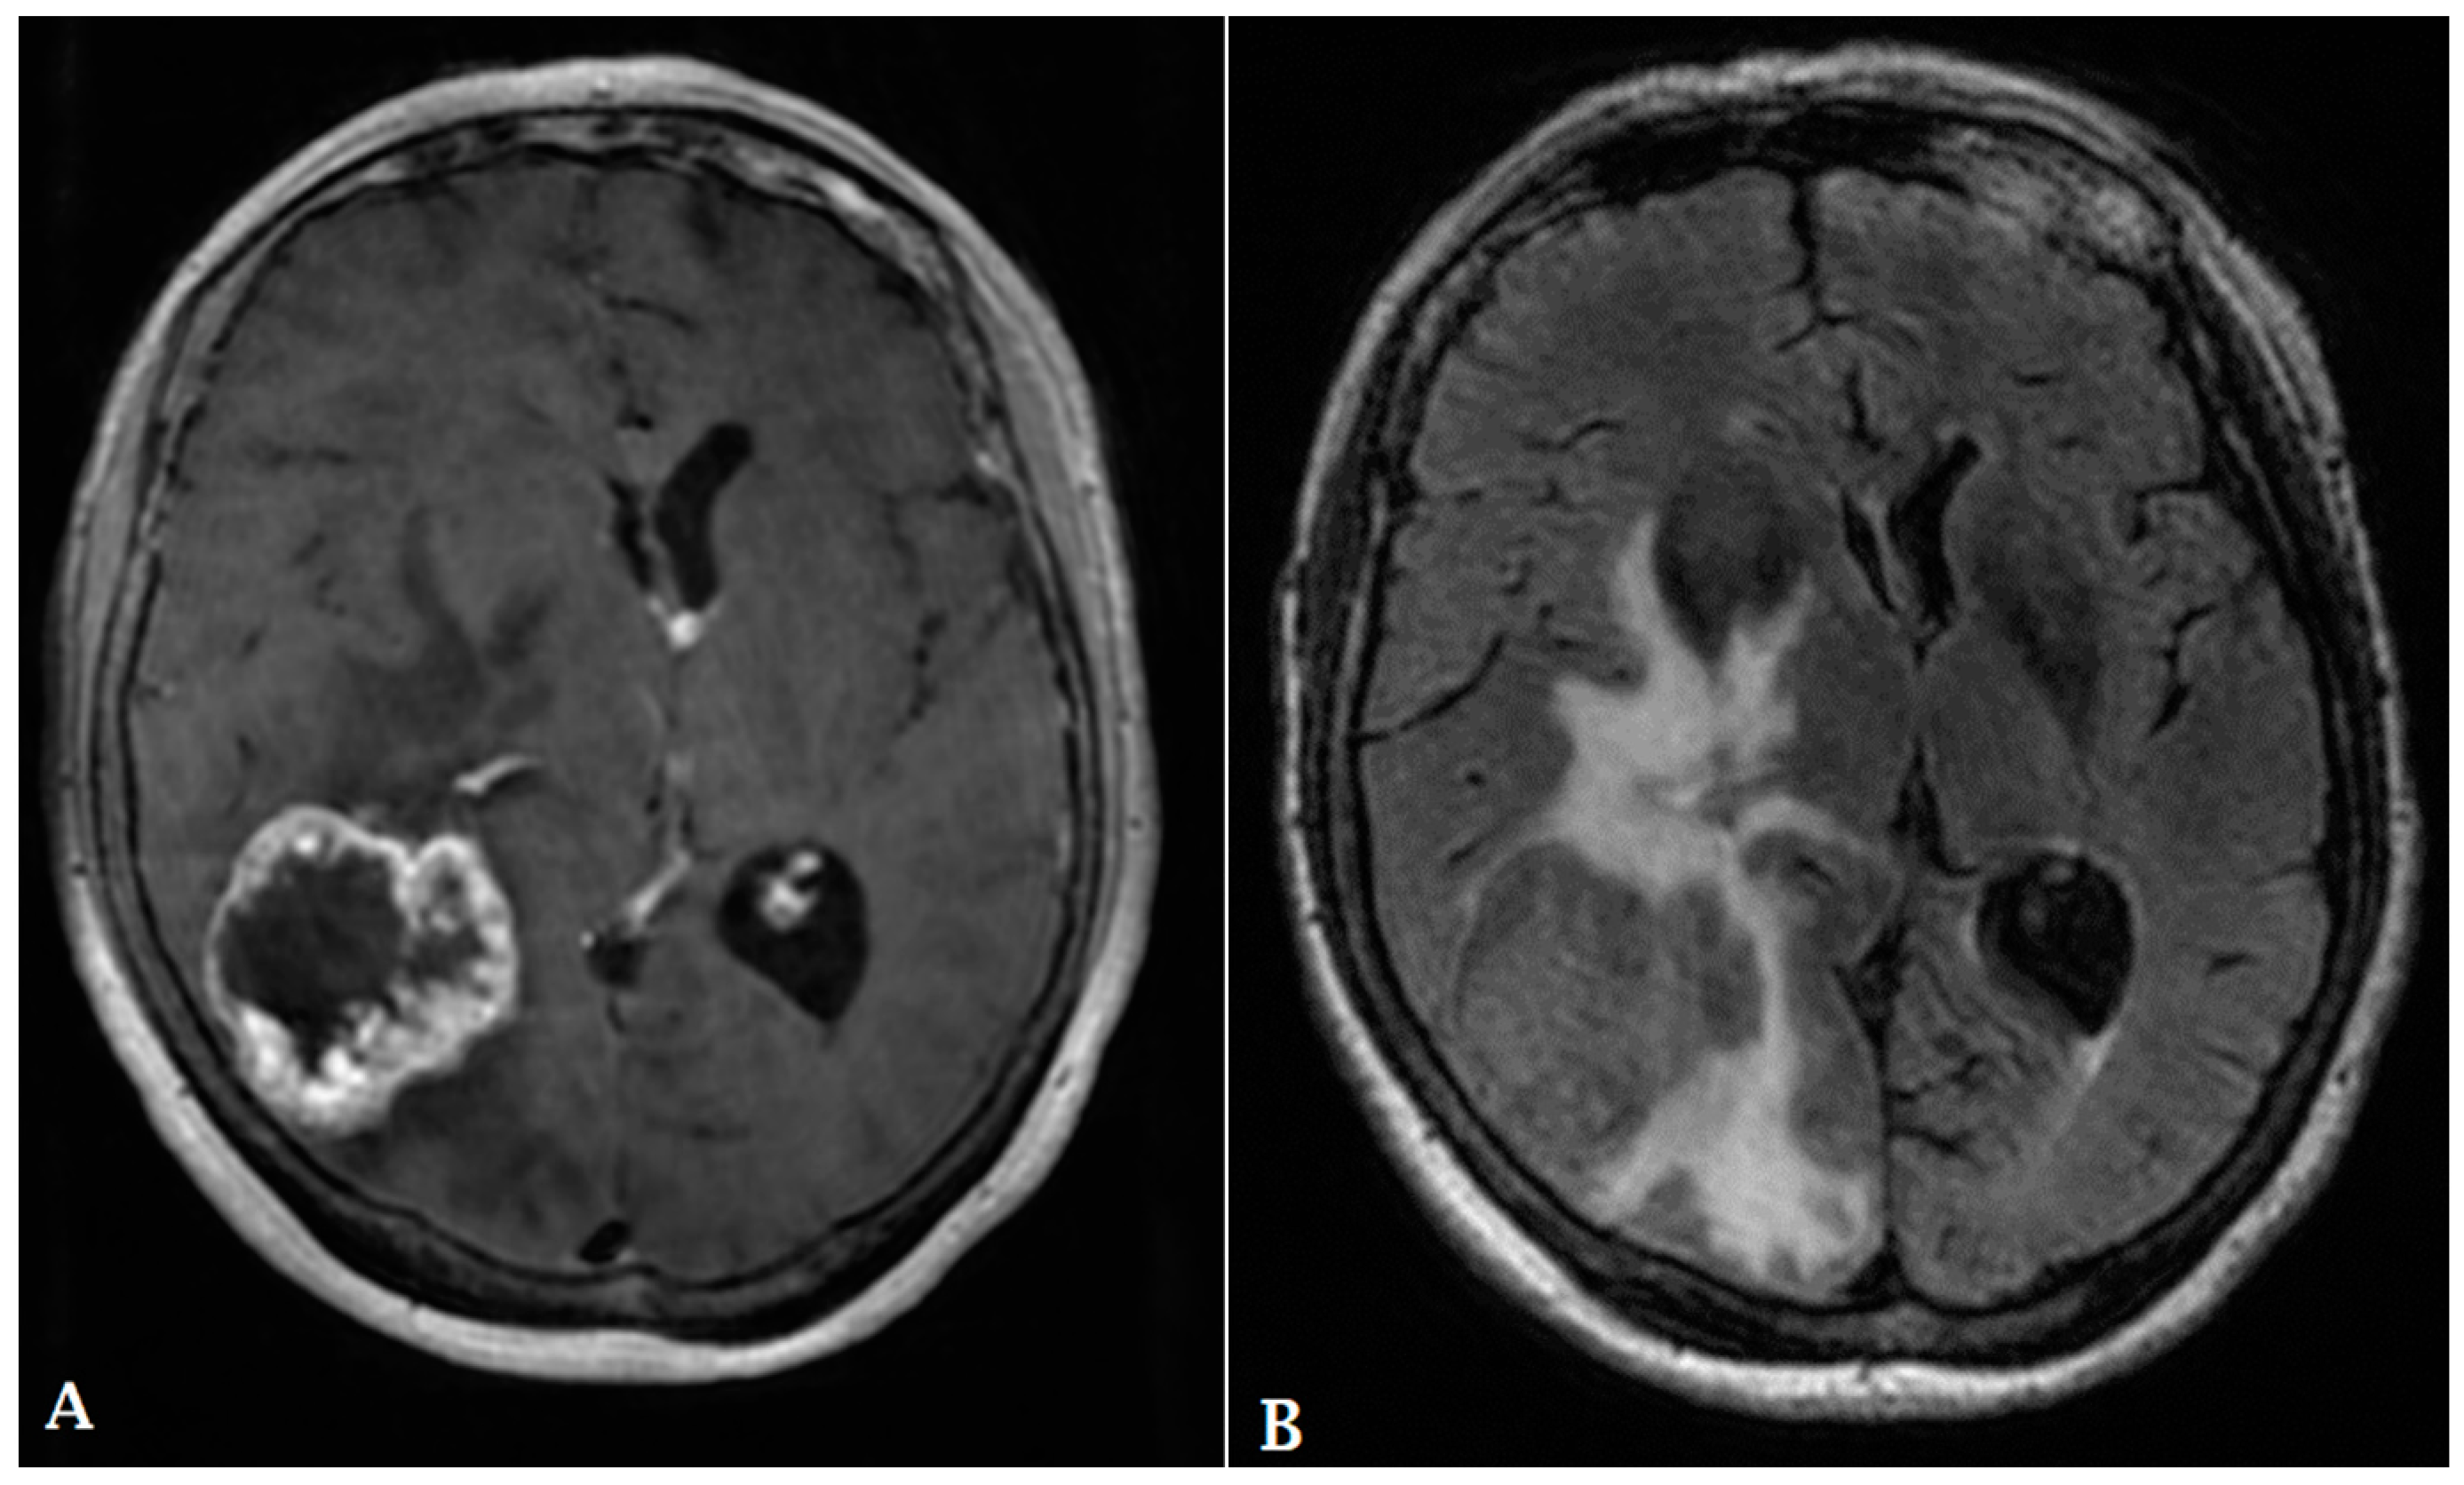

- Artzi, M.; Bressler, I.; Ben Bashat, D. Differentiation between glioblastoma, brain metastasis and subtypes using radiomics analysis. J. Magn. Reson. Imaging 2019, 50, 519–528. [Google Scholar] [CrossRef]

- Qian, Z.; Li, Y.; Wang, Y.; Li, L.; Li, R.; Wang, K.; Li, S.; Tang, K.; Zhang, C.; Fan, X.; et al. Differentiation of glioblastoma from solitary brain metastases using radiomic machine-learning classifiers. Cancer Lett. 2019, 451, 128–135. [Google Scholar] [CrossRef]

- Kickingereder, P.; Wiestler, B.; Sahm, F.; Heiland, S.; Roethke, M.; Schlemmer, H.-P.; Wick, W.; Bendszus, M.; Radbruch, A.; Jalaguier-Coudray, A.; et al. Primary Central Nervous System Lymphoma and Atypical Glioblastoma: Multiparametric Differentiation by Using Diffusion-, Perfusion-, and Susceptibility-weighted MR Imaging. Radiology 2014, 272, 843–850. [Google Scholar] [CrossRef]